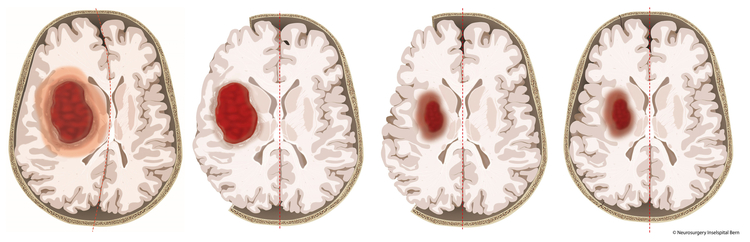

mp Groß-Gerau - Um schwere Druckschäden nach einer Hirnblutung zu verhindern, haben die Ärzte in der Studie temporär einen Teil des Schädelknochens entfernt. Universitätsklinik für Neurochirurgie / Inselspital Bern

Gerade tief im Gehirn liegende Blutungen haben meist massive Konsequenzen. Die Blutung und folgende Schwellungen üben Druck auf das umgebende Gehirngewebe aus und führen so zu weitreichenden Schäden im Gehirn. Eine wirksame Therapie gibt es bislang nicht. Nun gibt es erstmals wertvolle Hinweise auf einen wirksamen neurochirurgischen Ansatz, wie ein internationales Team um Ärzte der Universitätskliniken Freiburg und Bern zeigt: Sie fanden Hinweise, dass ein Öffnen der Schädeldecke und damit eine Druckminderung im Gehirn zu weniger schweren Verläufen führt.

Die SWITCH-Studie untersuchte daher gezielt die Wirkung einer Kraniektomie zur Druckentlastung bei besonders schwer betroffenen Patienten. Dabei wurde ein Teil der Schädeldecke entfernt und nach Rückgang der Schwellung wieder implantiert. Die Patienten erhielten entweder die bisherige Standardtherapie oder die Standardtherapie in Kombination mit der Dekompressions-Kraniektomie.